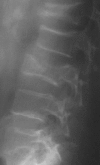

Case presentation: We describe two cases of non-traumatic acetabular and vertebrae fractures following seizures without history of epilepsy. They occurred in two male patients, 18 and 48 years old suffering respectively from hypercorticism and poorly controlled diabetes mellitus. Seizures, occurring inside hospital, were secondary to hypertensive encephalopathy crisis with hypokaliemia in the first case and severe hypoglycaemia in the second one. Fracture was promoted by a decrease in mineral bone density caused respectively by hypercorticism and diabetic chronic renal failure.